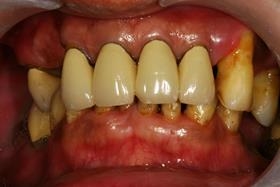

全口植牙重建

治療前,口內照片。